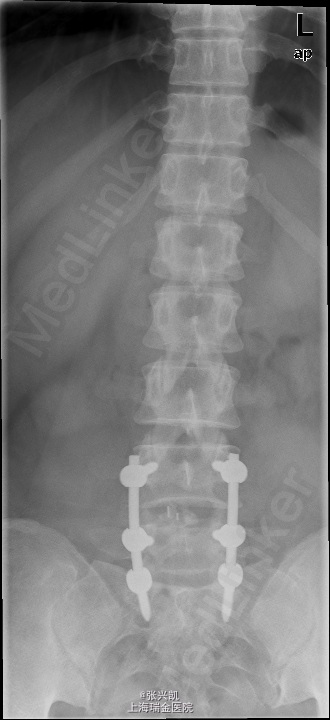

诊断: 1、腰椎椎间盘突出(L4-5,L5-S1) 2、腰椎椎管狭窄(L4-5,L5-S1) 处理: 经后路行L4-5,L5-S1椎管减压,椎间盘摘除,L4-5,L5-S1融合内固定术

随访:手术后一周即在医生指导下进行康复活动,卧床为主,一个月后解除腰围,进行基本生活劳动,3月后随访内固定器械位置良好,患者疼痛消失,一年后随访,患者椎体融合良好,双下肢感觉良好。 讨论:对于椎间盘突出压迫神经,时间较长,出现麻木等感觉的患者,应尽早手术解除压迫,有利于神经恢复,否则术后疼痛消失后,麻木的感觉可能一直存在,难以恢复。